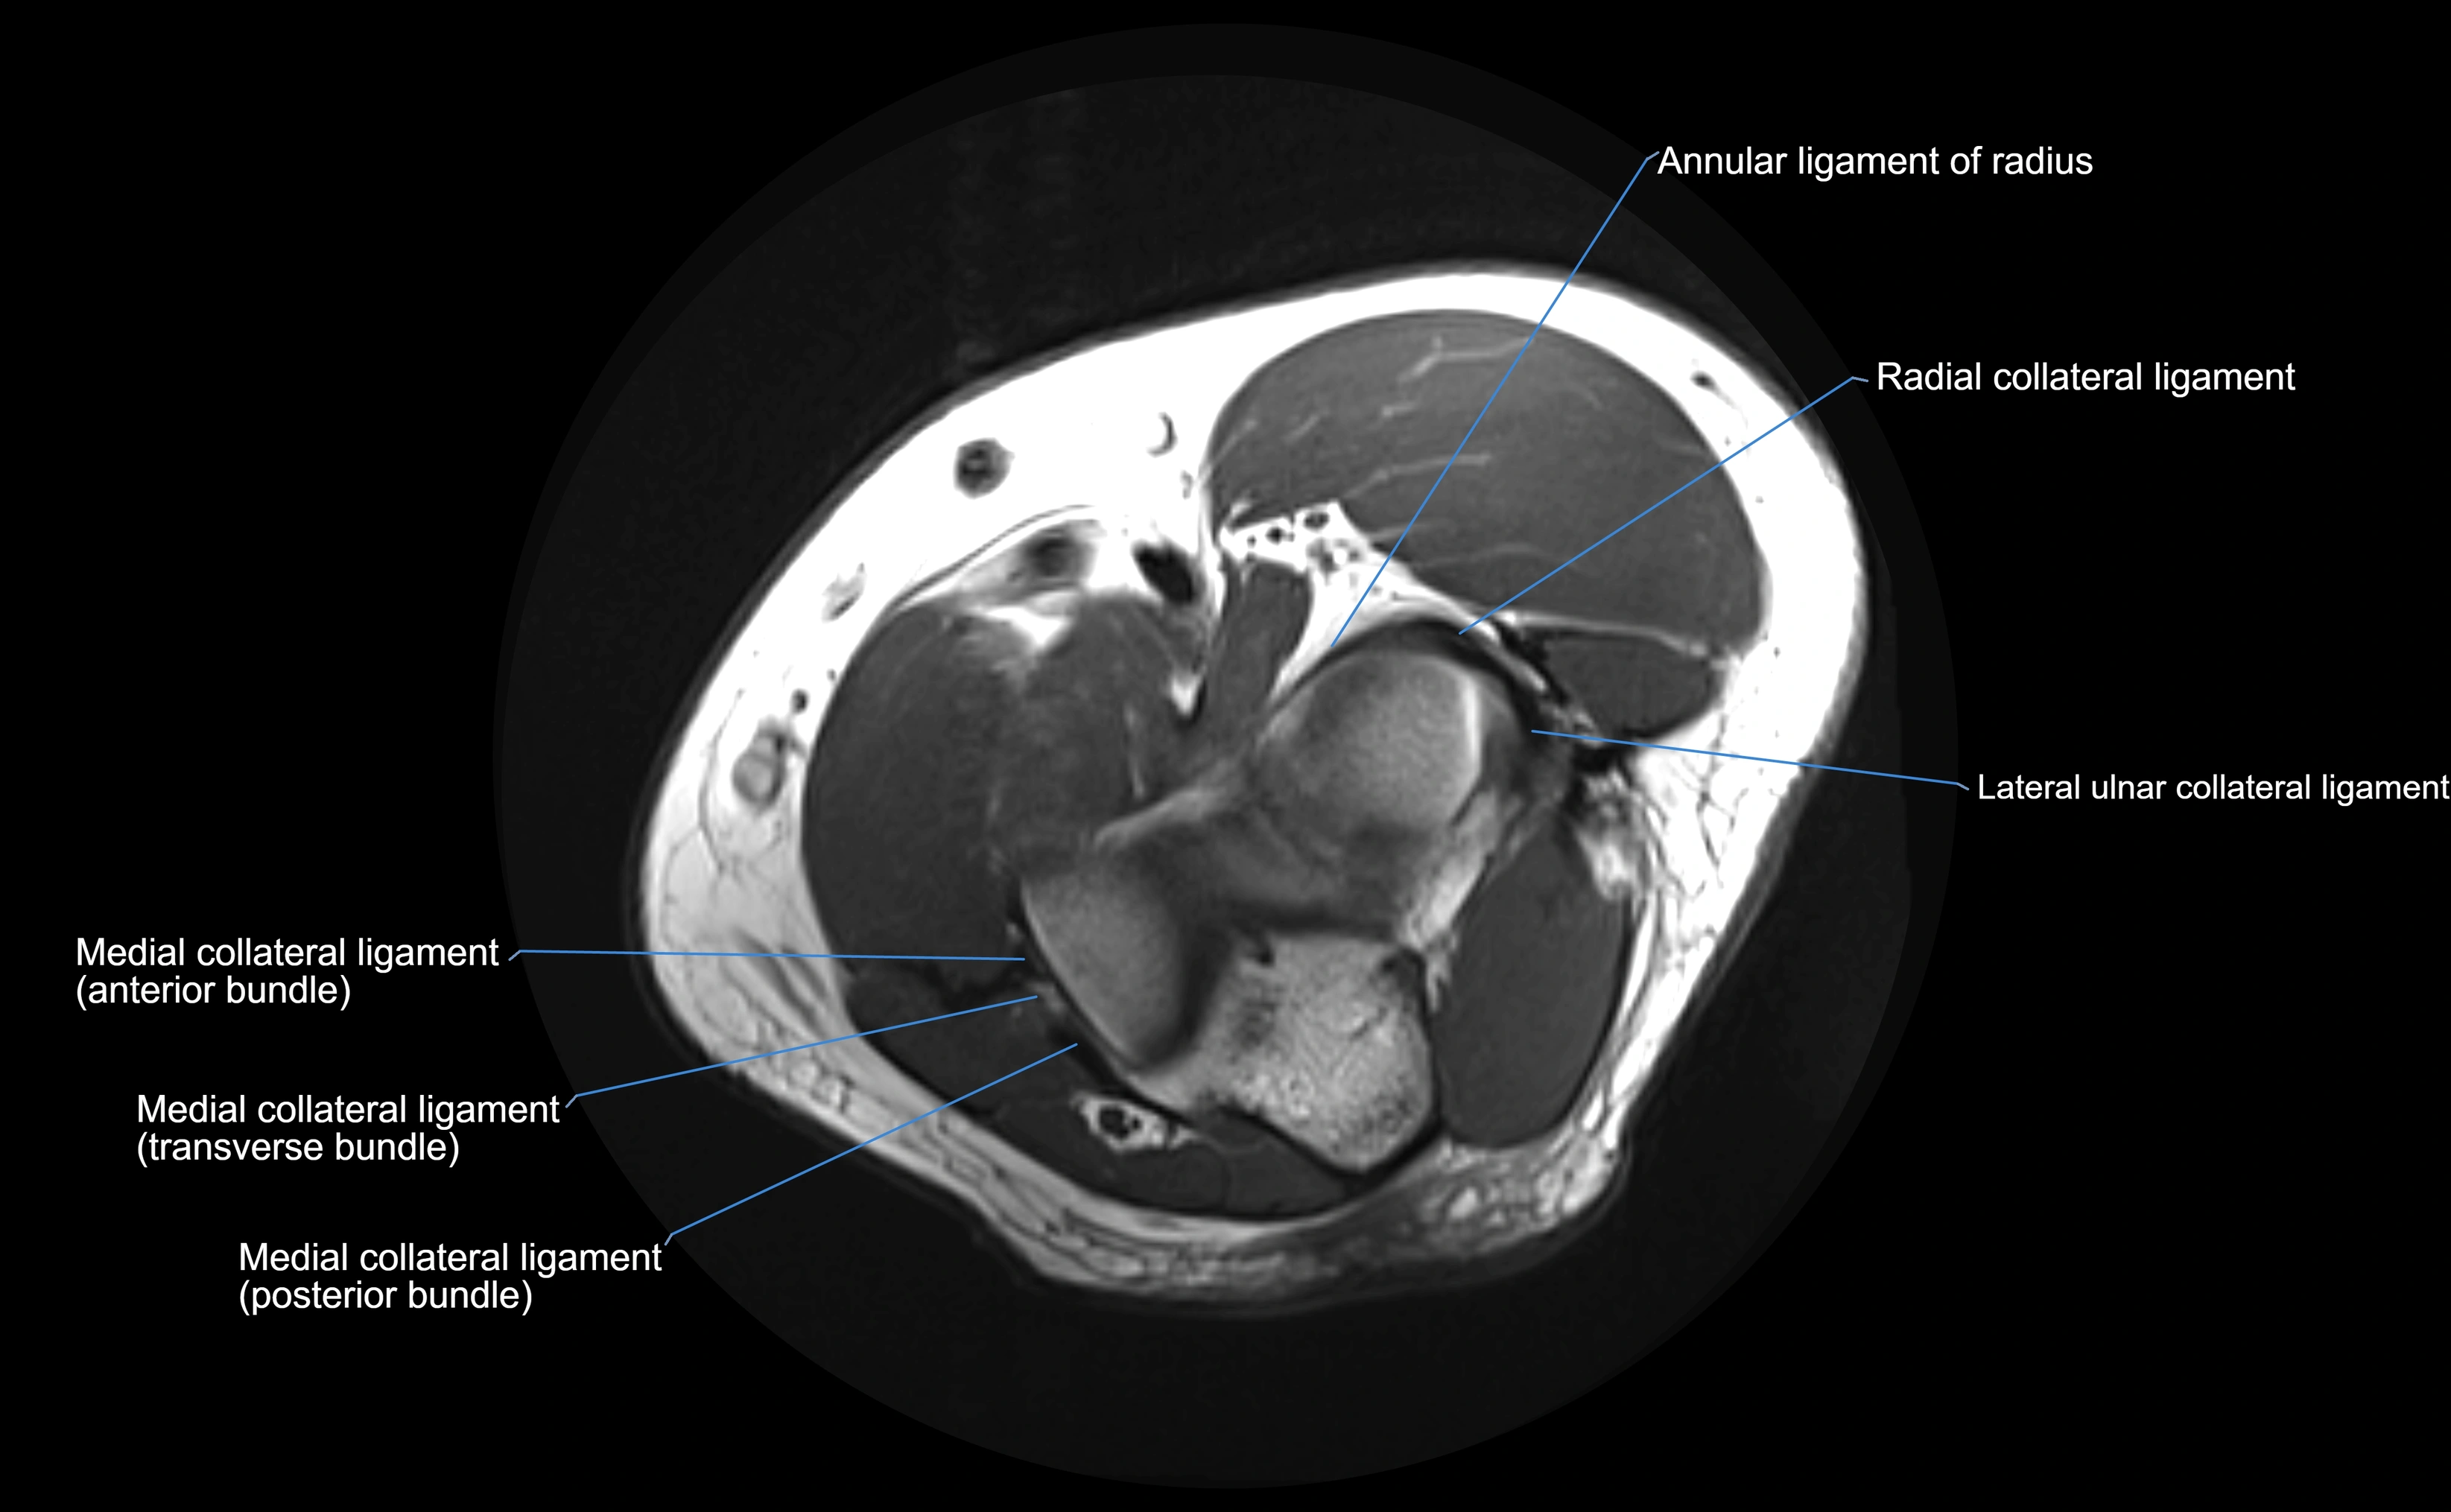

Annular ligament of radius

The annular ligament of the radius is a strong, circular band of fibers that encircles the head and neck of the radius, holding it securely against the radial notch of the ulna. It forms part of the proximal radioulnar joint, permitting smooth rotation of the radius during pronation and supination of the forearm.

The ligament acts like a collar or loop, maintaining radial head stability while allowing rotation. It is essential for forearm motion, elbow stability, and load transmission from the radius to the ulna and humerus.

Origin, Course, and Insertion

• Origin: Arises from the anterior margin of the radial notch of the ulna.

• Course: Forms a strong circular band that wraps around the radial head and neck, maintaining them within the radial notch.

• Insertion: Attaches to the posterior margin of the radial notch, completing a fibrous ring around the radial head.

• The inner surface of the ligament is lined with synovial membrane, allowing frictionless rotation.

Relations

• Superiorly: Blends with the capsule of the elbow joint.

• Inferiorly: Supported by the quadrate ligament at the neck of the radius.

• Medially: Attached to the ulnar radial notch.

• Laterally: In contact with the radial head and its articular cartilage.

• Anteriorly: Related to the radial collateral ligament of the elbow.

• Posteriorly: Continuous with the elbow joint capsule.